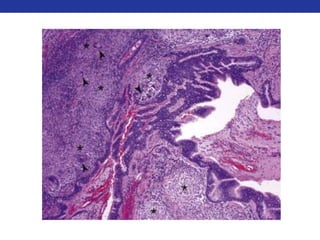

Adenoid Cystic Carcinoma

• Clinical features

• Most common malignant tumor of minor salivary glands

• Wide age distribution: 20 - 80 yo

• Median age = 50 yo

• Gross features

• Solid infiltrative pattern of growth

• Can invade nerves and move to brain

• Microscopic features

• Small, cuboidal, cytologically bland cells

• Arranged in cribriform patterns

• Some of the lumen-like spaces contain distinctive eosinophilic materia

• Prognosis: Poor, highly malignant, perineural invasion